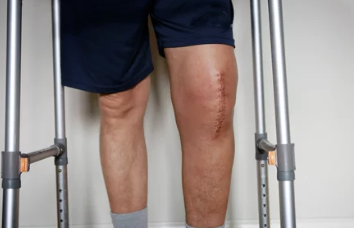

✔ 퇴행성 관절염이 심해지면 무릎 연골이 닳아 뼈끼리 부딪히며 심한 통증 유발

✔ 일상생활이 어려워지고 걷기조차 힘들어질 수 있음

✔ 수술을 통해 손상된 관절을 인공관절로 대체하면 통증 완화 & 활동 가능